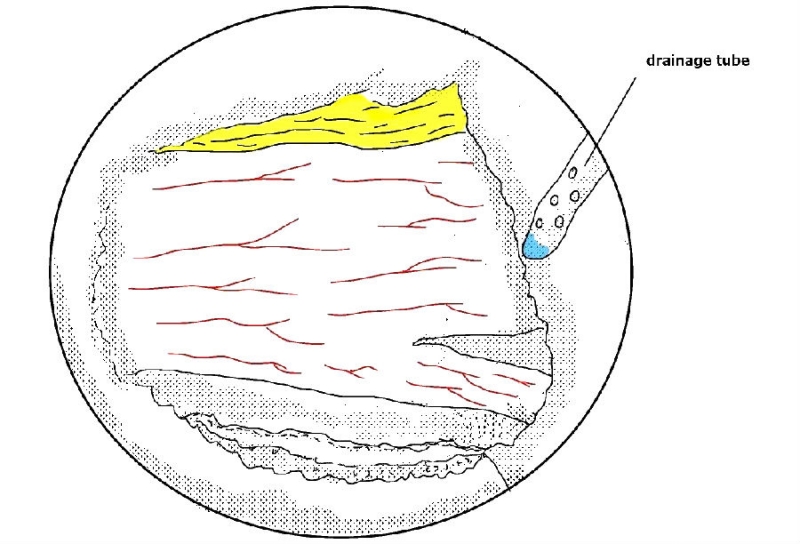

16. 在手术最后放置引流是好习惯,最好放置于椎板表面,不至于干扰神经根。

UBE处理椎管狭窄病例时,对于侧隐窝狭窄的患者,同侧减压范围与椎弓根内缘平齐即可。

从标本上看,椎弓根其实就位于终板的下方,这是术中判断椎弓根位置的解剖标志。

与椎间盘的下缘平齐即是椎弓根的上缘。

去除部分椎板上缘骨质尤其是与上关节突结合的部位利于黄韧带的切除及椎弓根内壁的显露。这个部位显露神经根的风险最小。